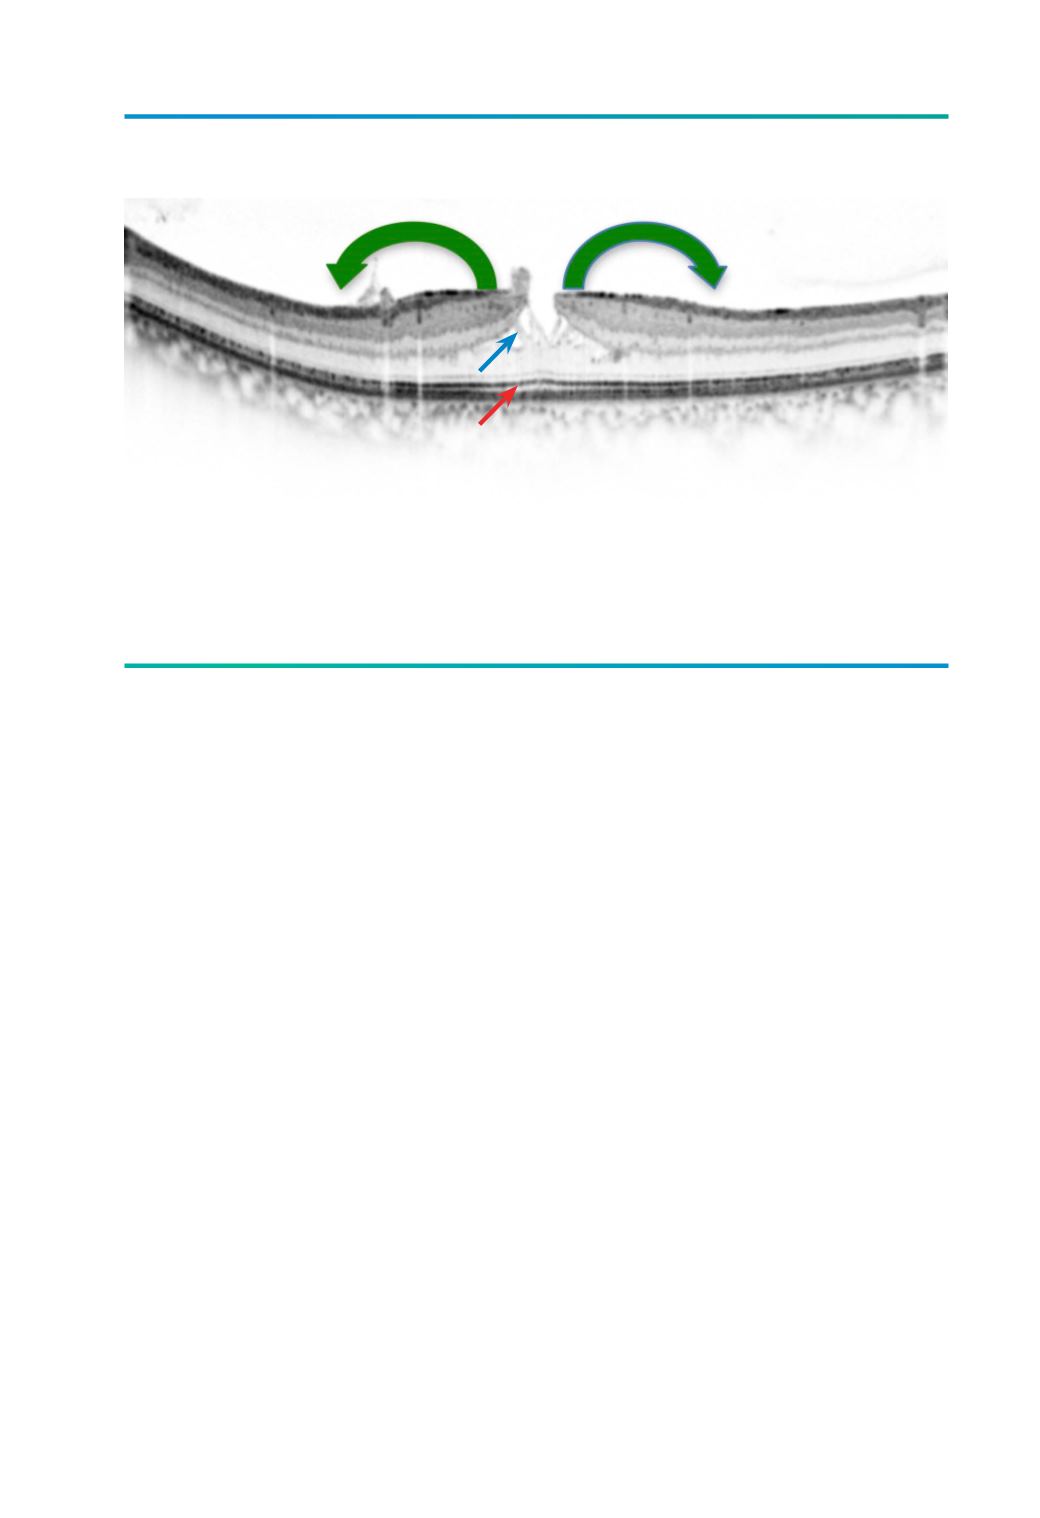

Figura 2.

Imagem de SD-OCT de buraco lamelar onde se pode observar a típica separação horizontal intra-retiniana,

entre a camada plexiforme externa e camada nuclear externa (seta azul) e a manutenção da integridade da

camada dos fotorreceptores (seta vermelha), importante para o diagnóstico diferencial com pseudoburaco

macular. Repare na tracção centrífuga exercida pela MER (seta verde).